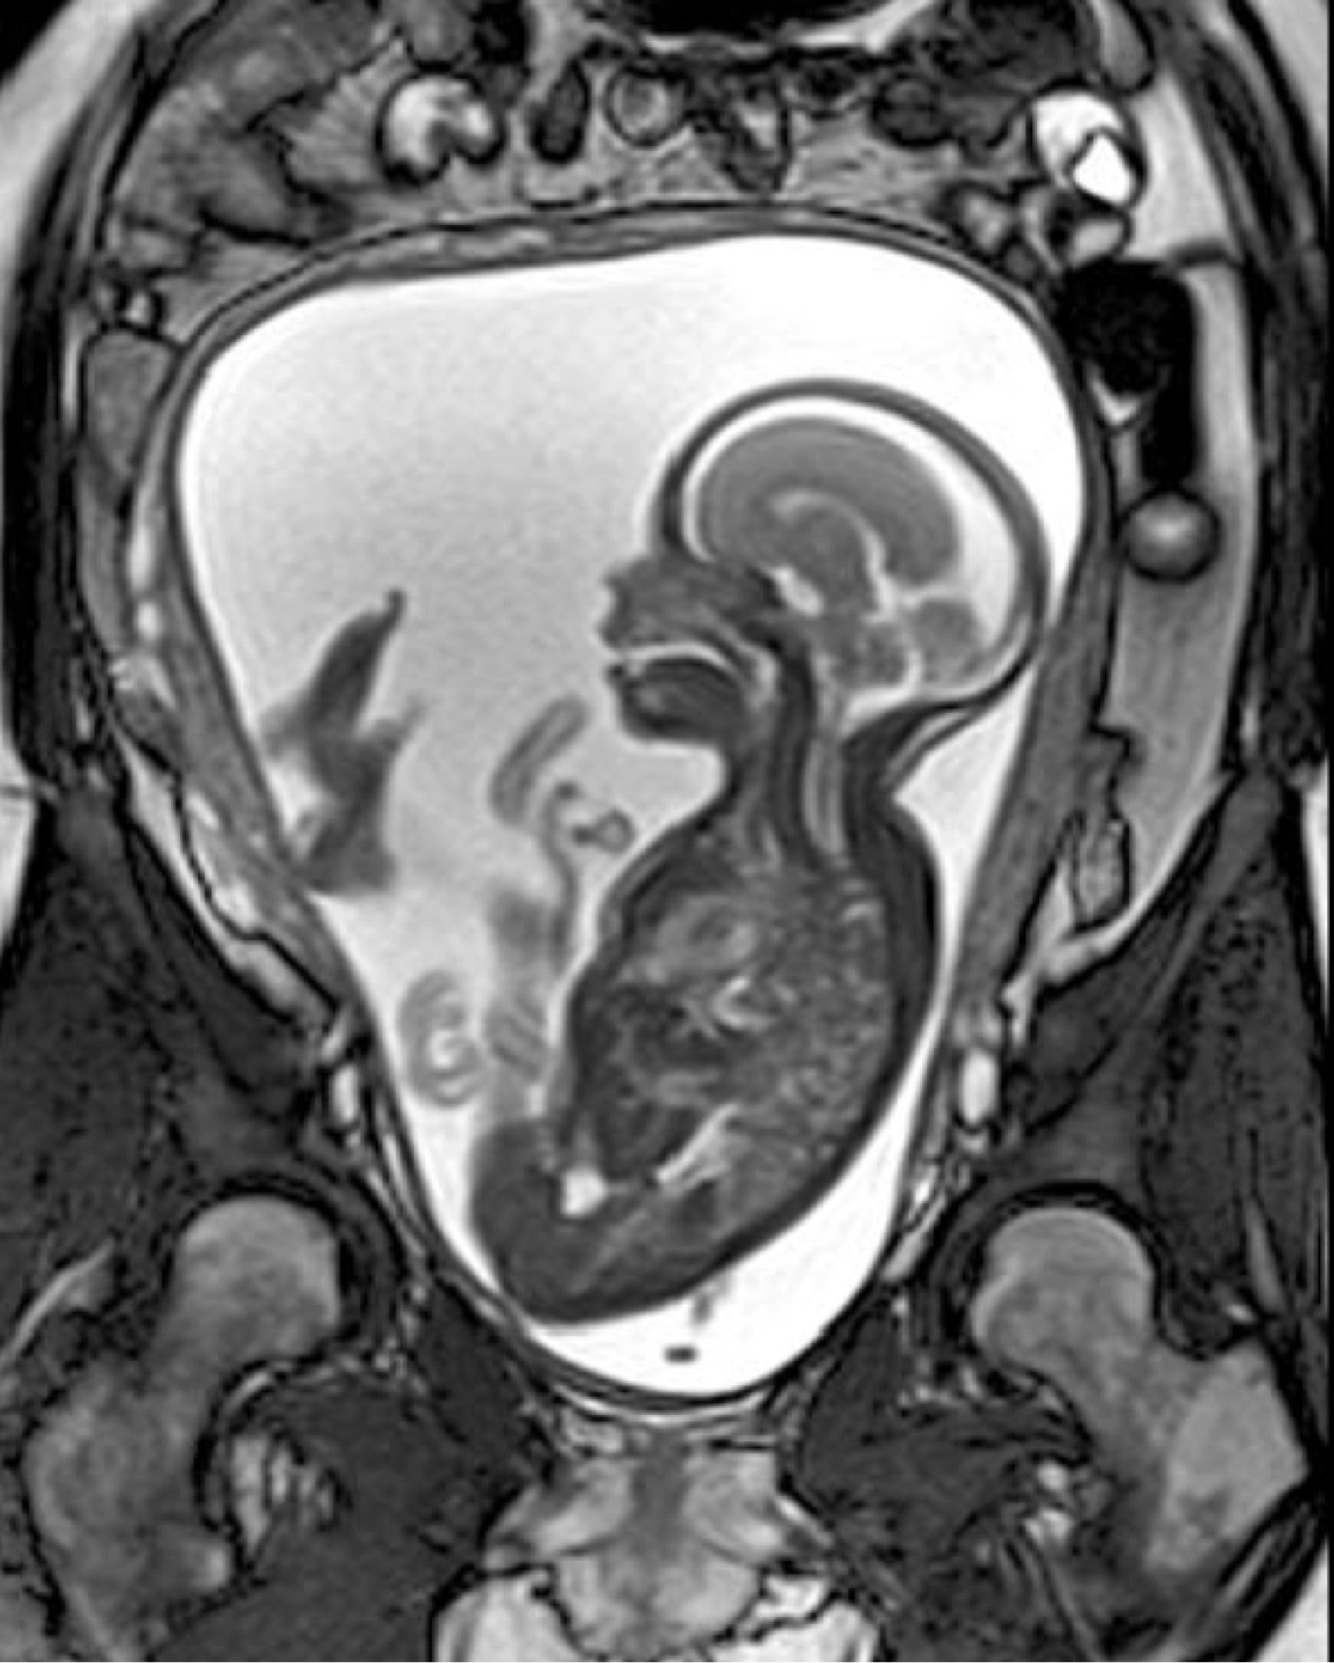

What can we see in this image?

A fetal MRI for CNS evaluation